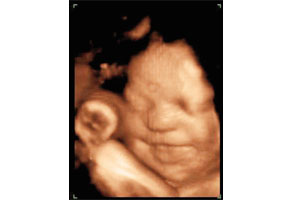

El ahora feto, a partir de la duodécima semana de gestación, sufre una serie de cambios notorios. No sólo triplica su peso, sino que también adquiere una forma más humana (a pesar de que su cabeza es más grande que su cuerpo). Sus ojos comienzan a desplazarse desde los lados de la cara hacia el frente y sus manos cuentan con los dedos y uñas desarrollados.

También es importante destacar que durante esta etapa el feto desarrolla una importante red celular, que le permitirá relacionarse con su entorno. Nos referimos al aumento de las neuronas ubicadas en el interior del cerebro, las que, durante el tercer mes, igualan la cantidad que posee un adulto. Si bien es un incremento importante, todavía no existen las conexiones necesarias para que el cerebro comande sus acciones.

Por ello, las acciones que el feto realiza, como cerrar los puños o tomarse las manos, son consideradas involuntarias.

Cerca del cuarto mes, la madre ya puede percibir los sutiles movimientos que realiza el feto. Poco a poco comienza a mover se y a flexionar las articulaciones de sus extremidades. Su corazón bombea cerca de 25 litros de sangre por día y sus piernas crecen aceleradamente, sobrepasando la longitud de los brazos. Se desarrollan las huellas dactilares y numerosos pliegues en el cerebro, así como también se endurecen los huesecillos del oído medio.

Su cuerpo está cubierto por un fino y suave vello llamado lanugo. Pero sin duda, el cambio más importante ocurre a nivel de los genitales, los que se desarrollan y permiten determinar el sexo del bebé.

El quinto mes trae consigo una novedad fundamental en lo que respecta a la interacción entre la madre y el feto. Este último es capaz de realizar enérgicos movimientos, detectables al tacto e incluso, visibles. No es raro que en el vientre materno se formen verdaderos «bultos», que pueden ser los puños o pies del bebé. Como sus órganos ya están casi formados, el feto desarrolla un sistema de defensa que le permite mantener la temperatura (gracias a la acumulación de grasa) y protegerse de algunos organismos patógenos (un atisbo de su sistema inmune).

Su aspecto, al final de estas semanas, será muy similar al de un recién nacido.